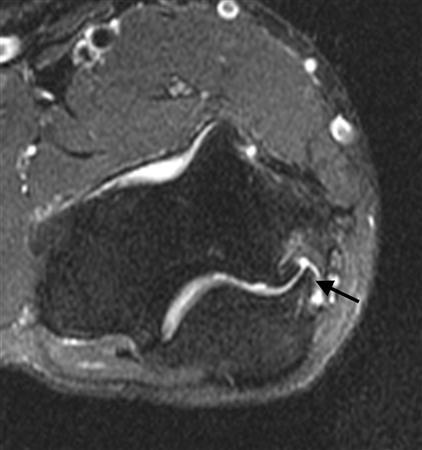

• MRI findings are helpful in confirming a UCL tear when suspected on physical exam. The “capsular T-sign” can be seen on MRI arthrogram in these patients, which is when contrast extravasates through the tear.

MR arthrogram in a pitcher what is this finding? Tx?

A

Ruputure of the medial collateral ligament. Medial UCL injury, full-thickness or partial undersurface tears capsular “T-sign” with contrast extravasation.

An MRI arthrogram of the elbow is shown in Figure 1. Based on these findings, what is the most likely diagnosis?

Rupture of the medial collateral ligament